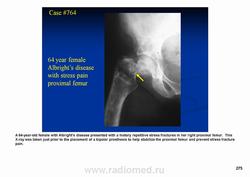

Фиброзная дисплазия — заболевание, характеризующееся нарушением развития (дисплазия) скелета, при котором нормальная кость замещается фиброзной тканью с элементами диспластически изменённой кости. Выделяют монооссальную (около 85% случаев), мономелическую (поражено несколько соседних костей одной конечности, плечевого или тазового пояса) и полиоссальную (около 5% случаев) формы. Фиброзная дисплазия как аномалия развития иногда сочетается с внескелетными расстройствами: 1) полиоссальная форма поражения сочетается с преждевременным половым созреванием и пигментными пятнами на коже в виде кофейных пятен (Albright’s syndrome); 2) сочетание фиброзной дисплазии с миксомами мягких тканей (Mazabraud’s syndrome). Встречается в любом возрасте, наиболее часто в первые 3 десятилетия жизни (70% больных). Монооссальная форма несколько чаще встречается у лиц мужского пола, при полиоссальной форме соотношение лиц мужского и женского пола 2 : 1. Поражается любая кость, наиболее частая локализация: проксимальная часть бедренной кости, большеберцовая и плечевая кости, рёбра, кости черепа, шейного отдела позвоночника. Поражение костей позвоночника только в 2,5% случаев.